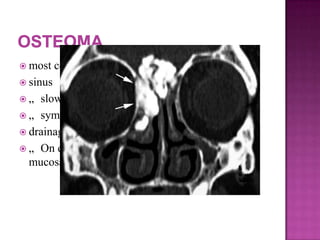

 most commonly localized to the frontal

 sinus

 „ slow growing and well circumscribed

 „ symptoms attributable obstruction of the

 drainage pathway of nearby sinuses

 „ On endoscopy : firm masses with a smooth

mucosal covering